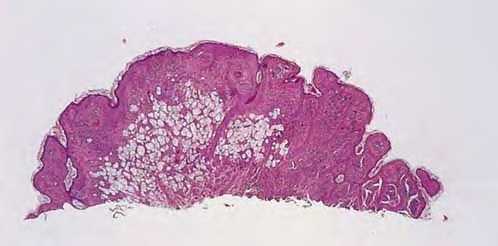

Balloon cells may be seen within the epidermis singly or in groups or may be absent from the epidermis. In the dermis, they lie arranged in lobules of varying size, often with an admixture of ordinary nevus cells and often with transitional forms between the ordinary and ballooned nevus cells . The balloon cells may be multinucleated and are considerably larger than ordinary nevus cells. Their nuclei are small, round, and usually centrally placed. Their cytoplasm appears empty, finely granular, or vacuolated, often with a few small melanin granules. There may be melanophages that are solidly packed with pigment. Stains for lipids, glycogen, and acid or neutral mucopolysaccharides are negative in the balloon cells. Electron microscopic examination reveals in balloon cells numerous large vacuoles formed by enlargement and coalescence of degenerating melanosomes . Balloon cell nevus is differentiated from balloon cell melanoma by the usual criteria. The large adipocytes present in some intradermal nevi as a result of fatty infiltration or stromal metaplasia differ from balloon cells by routine histology by having a flattened nucleus located at the periphery of the cell. In the differentiation from clear cell hidradenoma and other clear cell tumors, the absence of periodic acid-Schiff-positive glycogen and keratin in balloon cell nevus might be helpful; balloon nevus cells also stain for S100 protein, and although eccrine neoplasms (and adipocytes) may also express this marker, they will also usually be positive for Melan-AIMART-1 and negative for keratin markers.